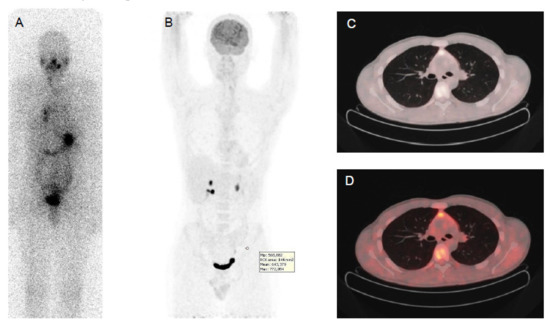

Figure 1.

Papillary thyroid cancer in a 41-year-old man with a high thyroid stimulating hormone stimulated serum thyroglobulin level (475 ng/mL). Post-therapy (A) 131I whole-body scan showed pulmonary uptake and uptake and in neck lymph nodes. 18F-FDG PET-CT (B,C,D): CT images evidenced multiple small millimetric lung metastases (B,C,D), without significant 18F-FDG uptake.

In DTC patients, the “flip-flop phenomenon” consists of a mismatch between high glucose and low iodine uptake, due to the elevated glucose metabolism coupled to the dedifferentiation process and has an important prognostic significance (Figure 2). This is observed in patients with iodine refractory thyroid cancer, with poorly differentiated, Hürthle cell cancer, PTC with aggressive features (tall cell variant) or with the BRAF V600E mutation and less frequently in patients with well differentiated papillary or follicular carcinoma. This indicates clinically more aggressive lesions [74,75,76] and the presence of 18F-FDG uptake in lesions with also radioiodine uptake indicates that these lesions are less likely to respond to radioiodine treatment [77].

Figure 2.

Papillary thyroid cancer in a 30-year-old woman. Post-therapy (A) 131I whole-body scan and 18F-FDG PET-CT (B,C,D) images. Post-therapy 131I whole-body scan did not show areas of uptake (A). 18F-FDG PET-CT images evidenced multiple areas of increased uptake in the left retrosternal and latero-cervical region.